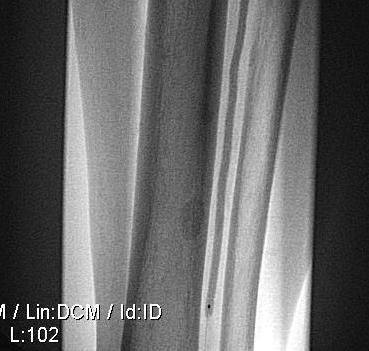

Операция

Реканализация МБА коронарным проводником, балонная дилатация баллоном Sleek